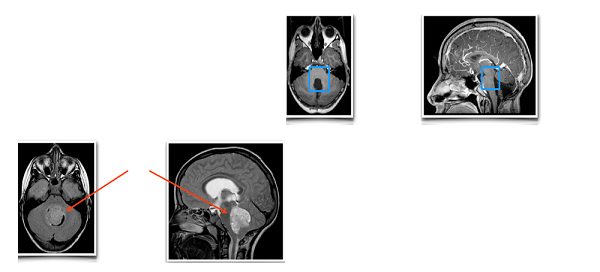

一名8岁男童因持续的头痛、呕吐就诊,起初家人认为只是疲劳和感冒造成的小问题,于是为其请假休养,但病情并未好转,甚至持续了三个月,患儿还出现了躯干性共济失调,走路不稳、举止异常笨拙,此时家人才发觉事态严重,就医后患儿被诊断为髓母细胞瘤,但由于病情凶险、位置深在,医院委婉建议转院、由更有经验的医生治疗。患儿家属查阅了很多论文和期刊后,决心前往INC国际专家、国际神经外科杂志《Journal of Neurosurgery》主编James T.Rutka教授所在的SickKids医院,并希望由Rutka教授为其制定综合治疗方案以延长患儿的生存期。

Rutka教授仔细研究了患儿的病历资料后决定先行手术近全切肿瘤,随后辅以颅脊髓照射和周期性化疗,患儿对此耐受良好,并且带瘤生存长达8年之久,随访显示其顺利入学,虽然仍在接受后续治疗,但患儿一家认为“他已经足够幸运,感谢Rutka教授挽救了孩子的生命”。